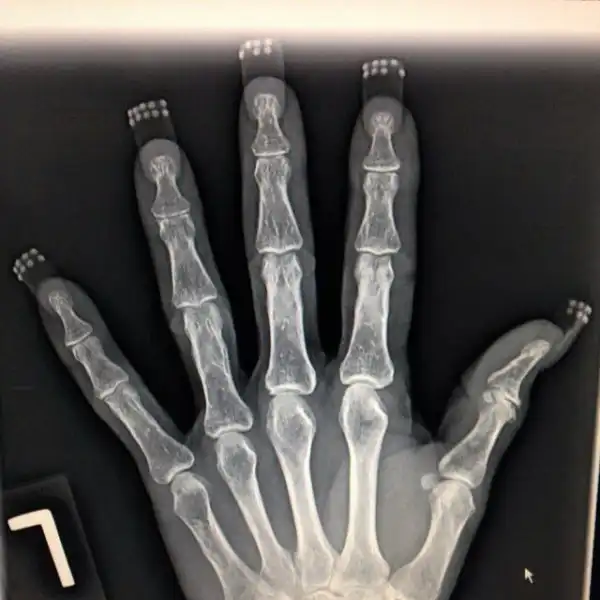

Девушки и маникюр/педикюр